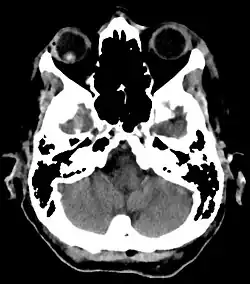

Traumatische Linsenluxation in der Computertomographie: Rechts (im Bild links) ist die röntgendichtere (im Bild hellere) Linse nach hinten in den Glaskörper verlagert. Links bestand bereits ein Zustand mit Kunstlinse, die in der Computertomographie hier nicht sichtbar ist.

Die Linse ist durch den fehlenden Zug der Zonulafasern verkleinert und abgerundet. Sie ist im Bezug auf die optische Achse und der Pupillenmitte nicht mehr zentriert. Bei Syndromen (Marfan oder Marchesani) kann sie nach oben verlagert sein, bei primärer Zonulainsuffizienz (insbesondere beim Pseudoexfoliationssyndrom) eher nach unten. Bei Fehlen von Zonulafasern z. B. durch Traumata (insbesondere typisch sind Kuhschwanzverletzungen) bestehen Zitterbewegungen (Phakodonesis). Wenn die Linse vollständig luxiert ist, besteht ein Aphakiestatus mit einer Hyperopie (bei normaler Augapfellänge zwischen 10 und 16 Dioptrien). Die Linse findet man dann im Glaskörperraum, seltener auch in der Vorderkammer.